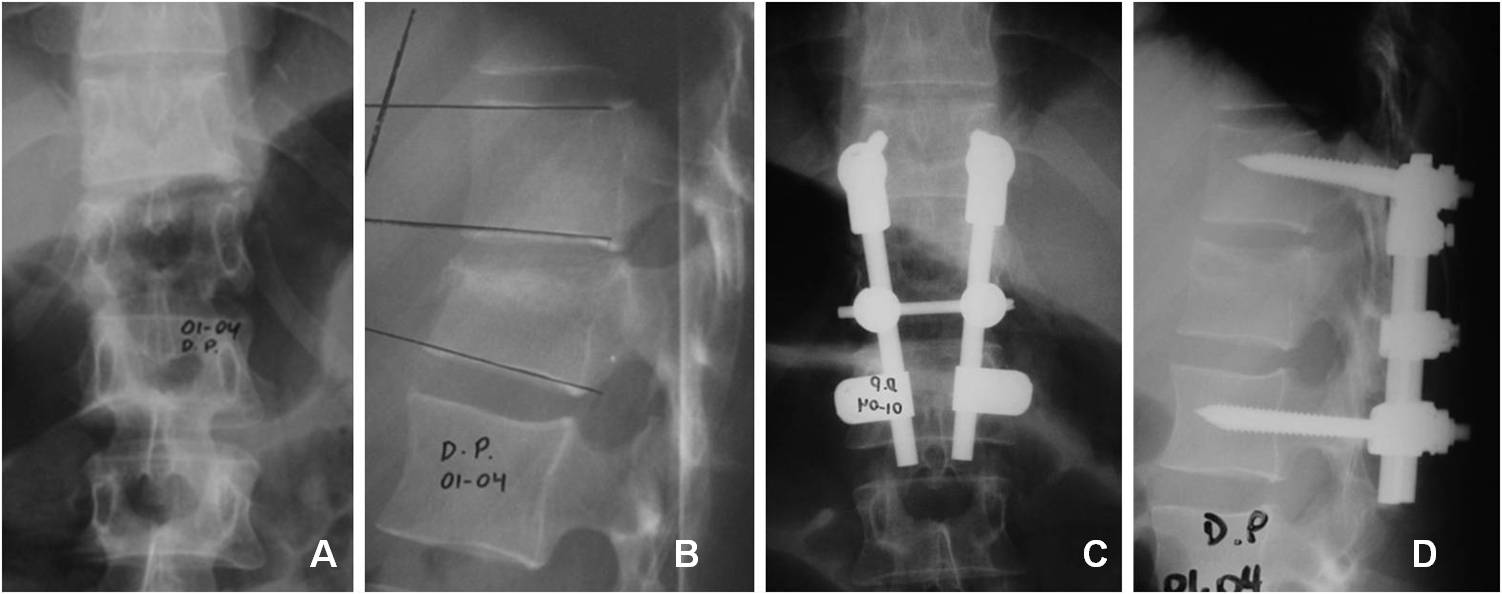

Introducción: El tratamiento quirúrgico de las fracturas toracolumbares es controvertido. La vía de abordaje y la cantidad de niveles de instrumentación son motivo de debate. El objetivo de este estudio fue analizar los resultados radiológicos y clínicos de pacientes con fracturas toracolumbares por estallido y flexión/distracción.MaterialesyMétodos: Estudio retrospectivo de una serie consecutiva de pacientes tratados quirúrgicamente entre 2004 y 2008, con seguimiento >12 meses. Se incluyeron pacientes con instrumentación y artrodesis corta de los niveles adyacentes a la lesión, abordados por vía posterior. Se tomaron en cuenta fracturas de tipo A3 y B de la clasificación AO. Se llevaron a cabo evaluaciones clínica, neurológica y radiológica.Resultados: Se registraron 25 pacientes, 3 se perdieron en el seguimiento y 22 fueron analizados. El promedio de edad fue de 37 años. La causa más frecuente fue caída de altura, seguida de accidente vehicular. El nivel más afectado fue L1. El promedio de cifosis preoperatoria fue de 14º y de 4º en el posoperatorio alejado. En la evaluación clínica, 10 pacientes tuvieron un excelente resultado; 10, bueno y 2, regular. No hubo compromiso neurológico en 21 pacientes.Conclusiones:La instrumentación corta proporciona muy buenos resultados en la mayoría de los pacientes tanto a nivel radiológico como funcional. La selección de los pacientes debe ser estricta, se debe excluir a aquellos con cifosis grave, conminución importante u otro factor que haga pensar en la necesidad de un abordaje anterior. En el seguimiento alejado, no se observa una pérdida significativa de la reducción en la cifosis.Descargas